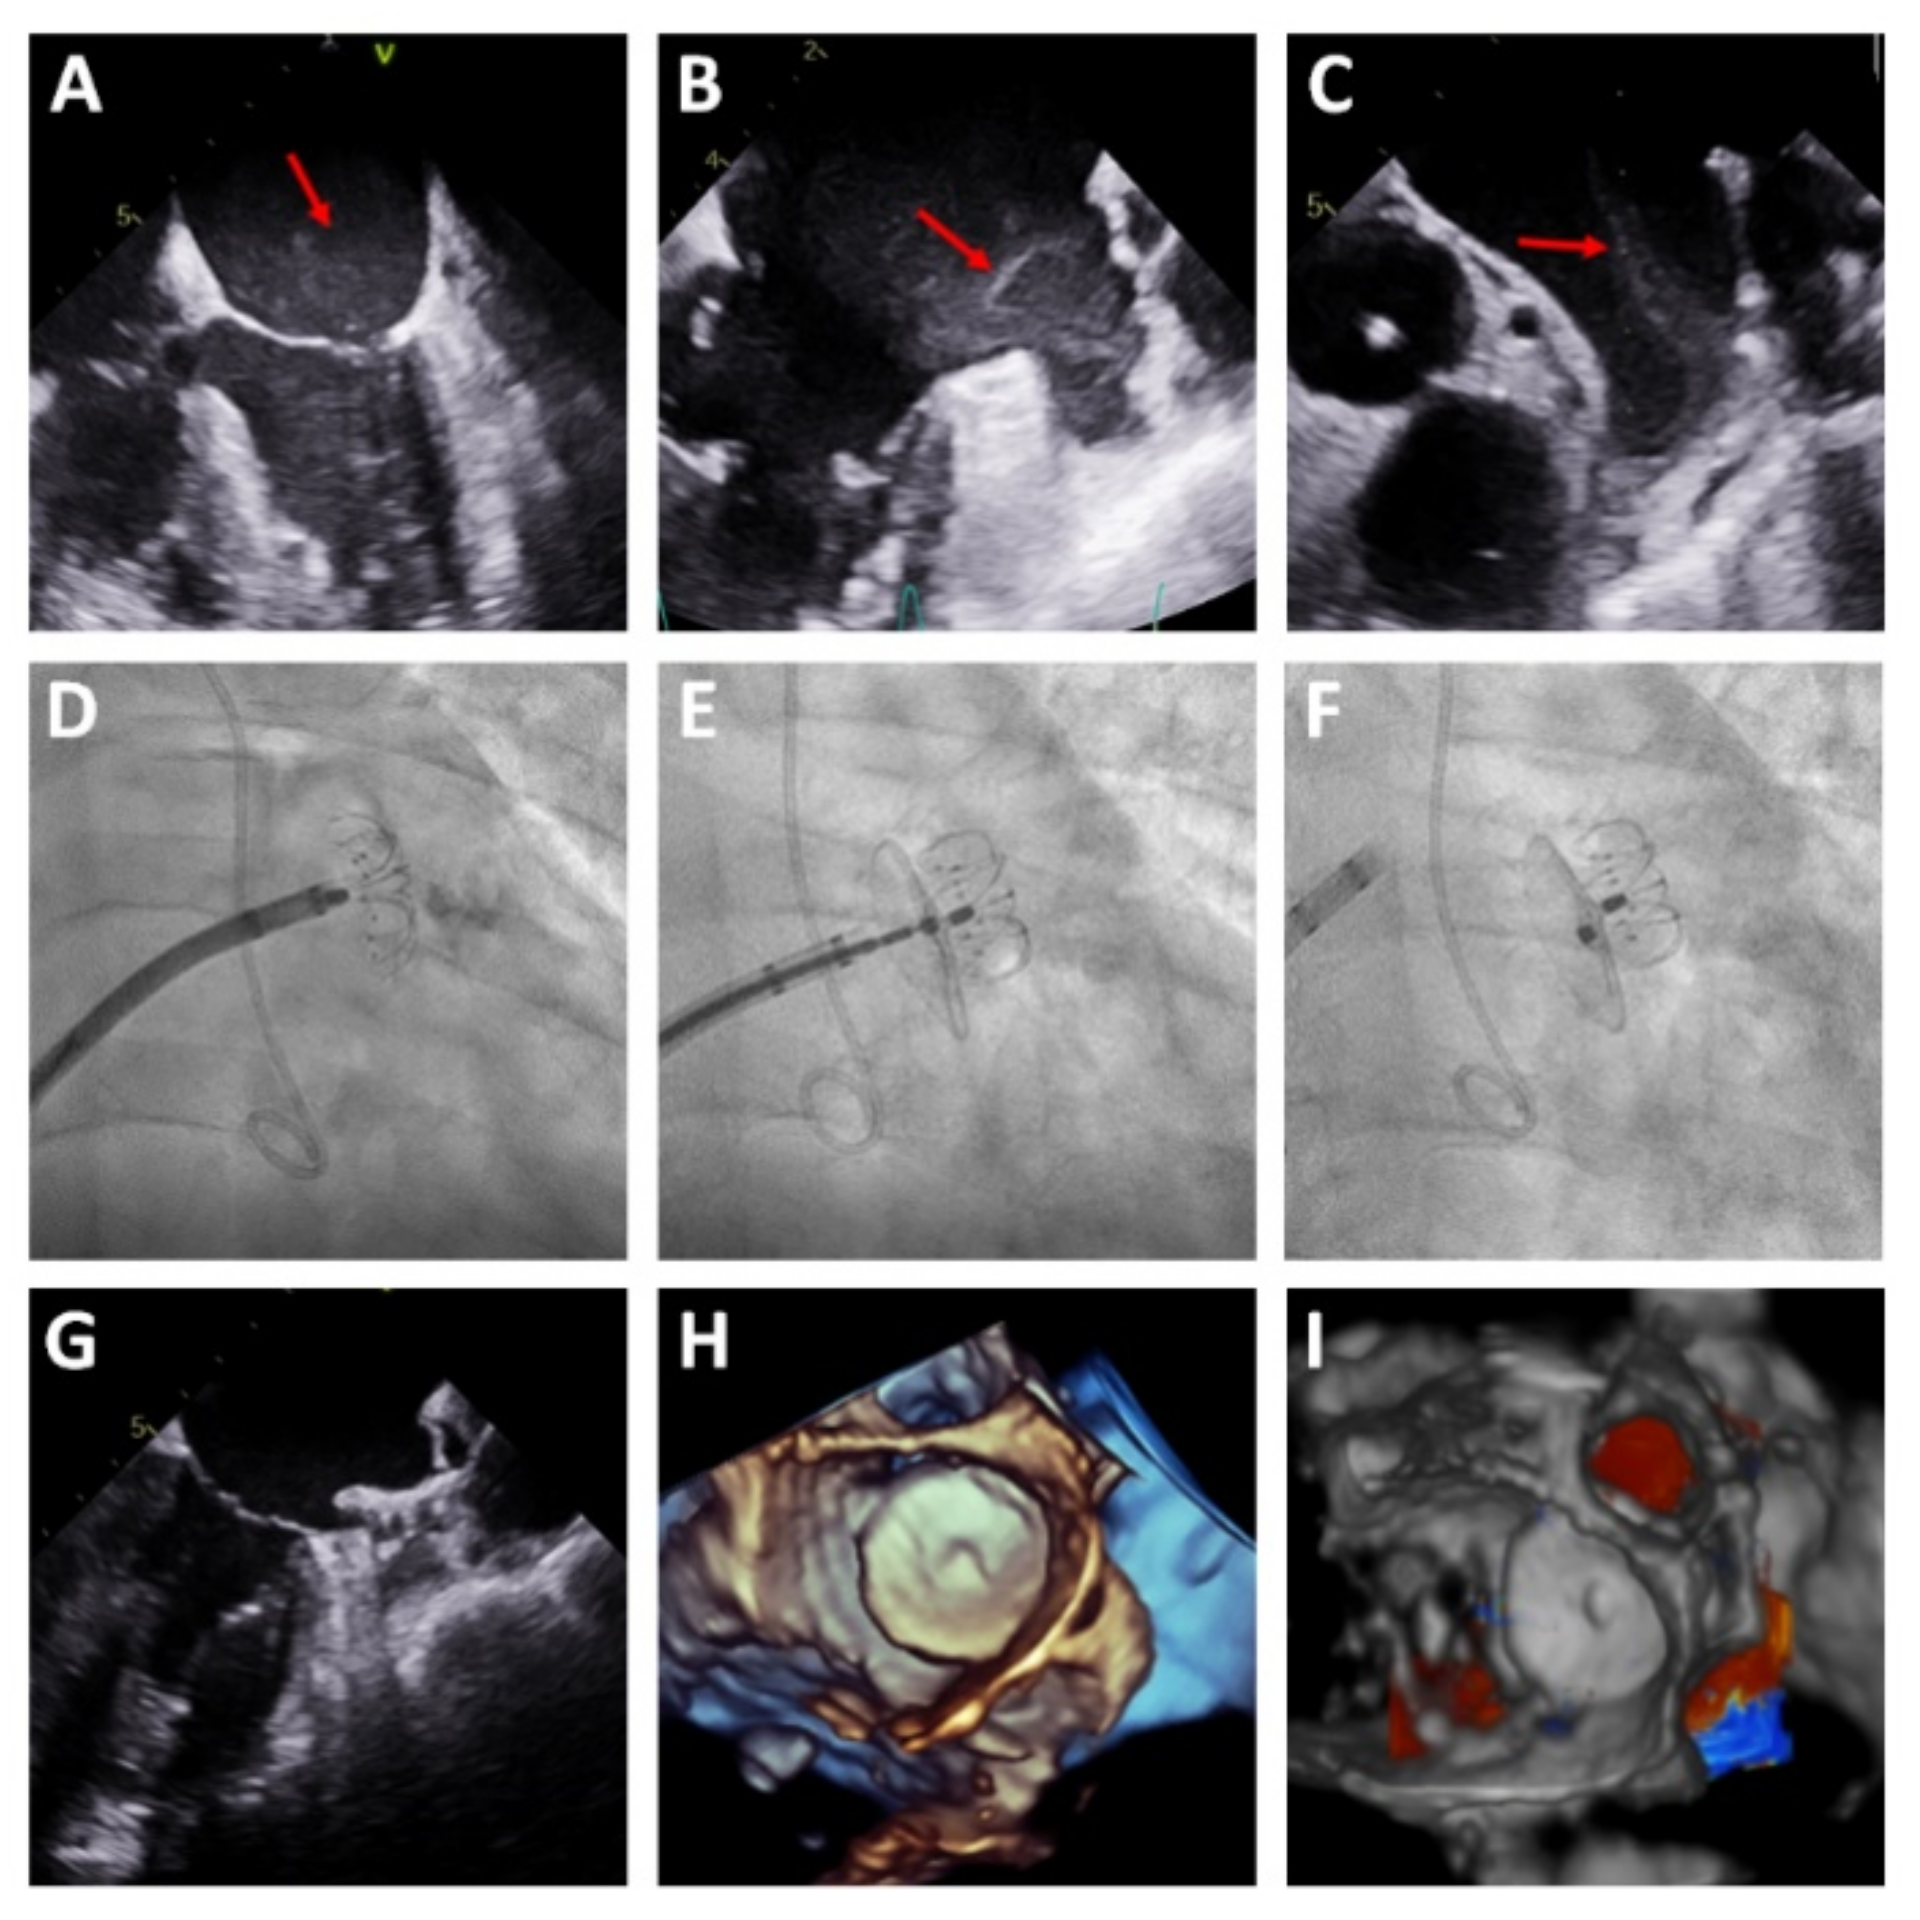

Figure 3. LAAC with early thrombosis. (A) TEE suggestive of “smoke” in the left atrium (red arrow). (B,C) Smoke/early thrombosis in the LAA (red arrow). (DF) LAAC guided exclusively by TEE. (G) TEE verification of the correct implantation of the device. (H,I) 3D TEE showing the LAAC device without a peridevice leak.

Procedural characteristics are detailed in Table 2. Most procedures (94.5%) were performed under general anesthesia and TEE guidance. Per protocol, coronary angiography was performed before the LAAC in the same session in all patients with unknown coronary anatomy. In three patients, the LAAC was performed in the presence of early thrombosis in the LAA; in these patients, the procedure was guided by TEE alone, without contrast injection (Figure 3). Procedural success was achieved in 54 patients (98.2%) and no patients were excluded due to complex LAA morphology. Device success was achieved in 100% of patients in whom device implantation was attempted (54 patients). In one patient, the device implantation was not attempted due to cardiac perforation while performance intracardiac echocardiography, requiring emergency surgery.